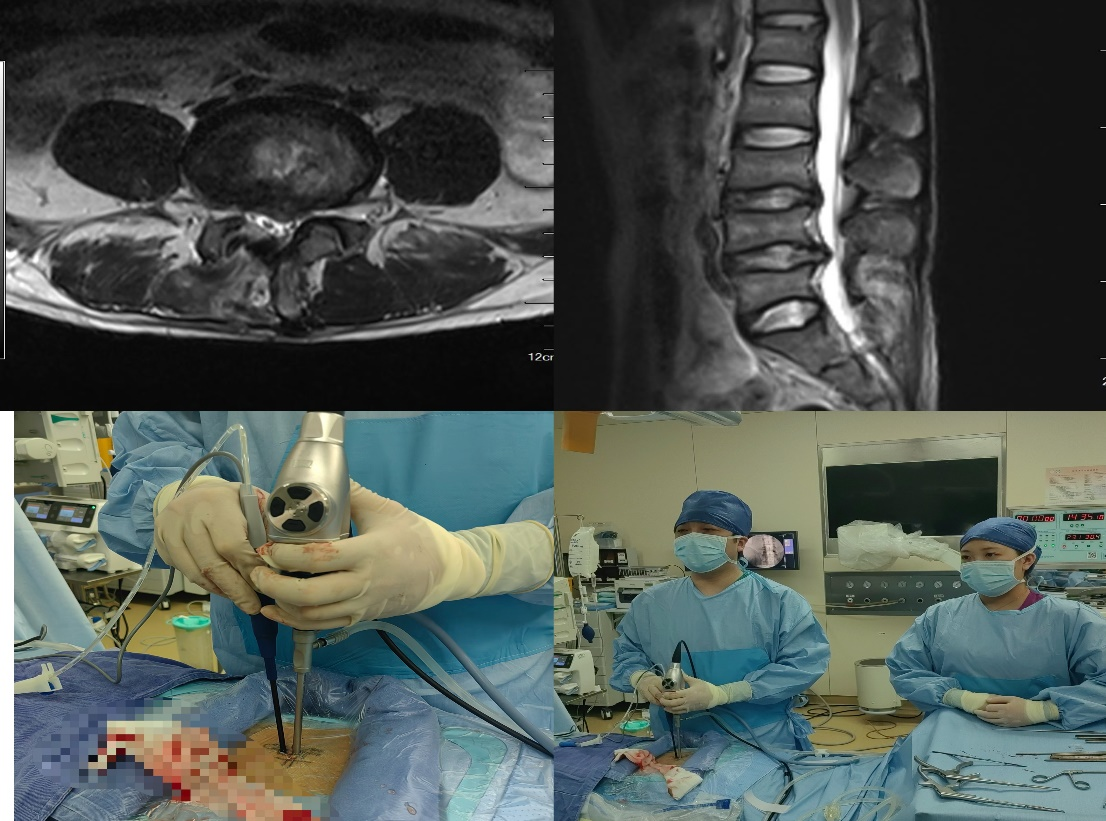

腰椎MRI結(jié)果顯示,陳先生的第4節(jié)腰椎和第5節(jié)腰椎的椎間盤(pán)突出嚴(yán)重,且髓核向椎管內(nèi)脫垂,已經(jīng)壓迫到了神經(jīng)根,需手術(shù)治療。入院前,陳先生依舊非常擔(dān)心:有沒(méi)有不開(kāi)大刀,微創(chuàng)治療腰椎間盤(pán)突出的手術(shù)方式呢?

完善術(shù)前準(zhǔn)備后,在麻醉科和手術(shù)室的大力配合下,由骨科朱迪主任醫(yī)師、王磊主任醫(yī)師主刀 ,短短1個(gè)小時(shí)左右便順利為陳先生摘除了壓迫神經(jīng)根的腰椎間盤(pán)髓核。手術(shù)全程在內(nèi)鏡的清晰、放大視野監(jiān)視下完成,手術(shù)部位的切口僅有1.5厘米大小,實(shí)現(xiàn)了少出血、少剝離、高效率的預(yù)期效果。